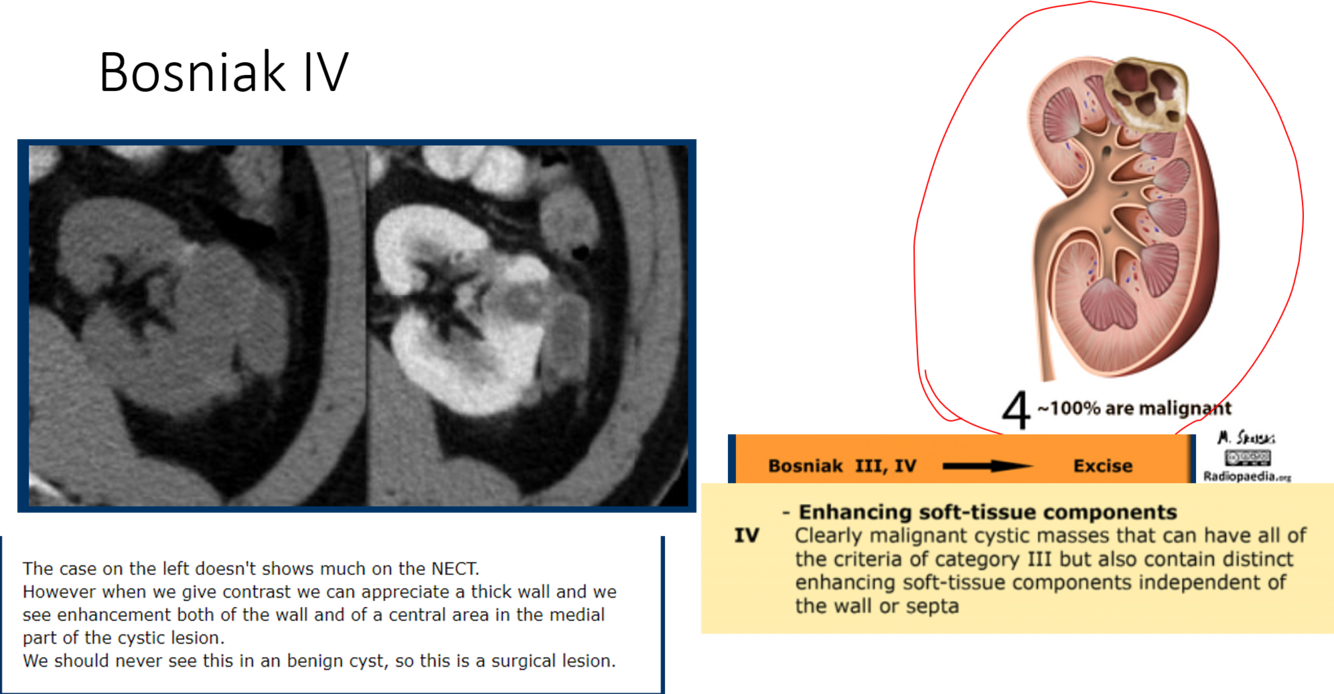

bosniak classifcation?

which bosniak classifications do you excise?

3 and 4